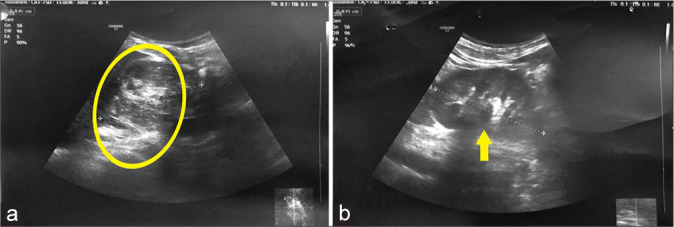

Renal replacement lipomatosis (RRL), as described by the word, is characterized by abnormal proliferation of the fatty tissue and replacement of renal parenchyma by fat with atrophy of renal parenchyma. This rare condition is mainly attributed to a long-standing disease such as lithiasis. The patient usually presents with non-specific abdominal pain of chronic duration, and imaging is necessary to confirm the diagnosis. Here, we present the case of total RRL presented at our center, diagnosed with ultrasonography, and computerized tomography of kidneys, along with contributing factors and its course of treatment.